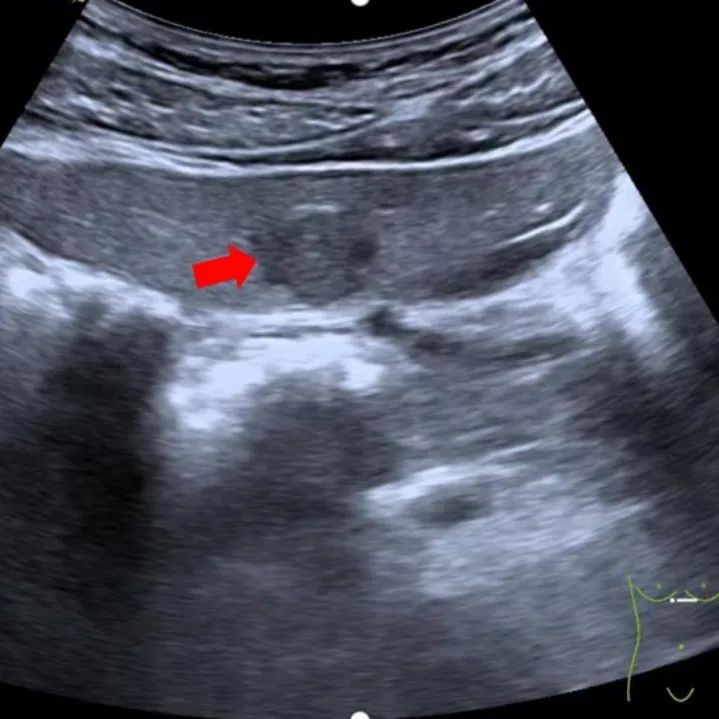

常规超声表现:大部分形态规则(类圆形)、边界清,低或稍低回声或等回声为主,高回声少见,合并脂肪肝时,基本为低回声。回声均匀或不均匀,少部分中央可见星状或条状低回声,部分周边见低回声晕环(此类容易误诊为恶性肿瘤)。

肝左外叶低回声病灶